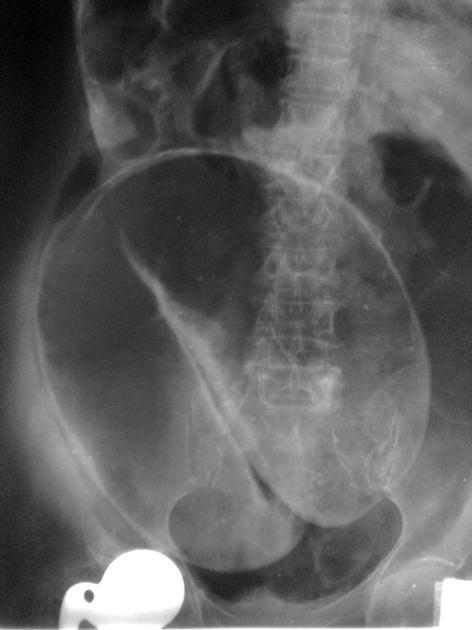

Sigmoid volvulus x-ray

Often done first line even though less sensitive than CT

Coffee bean sign